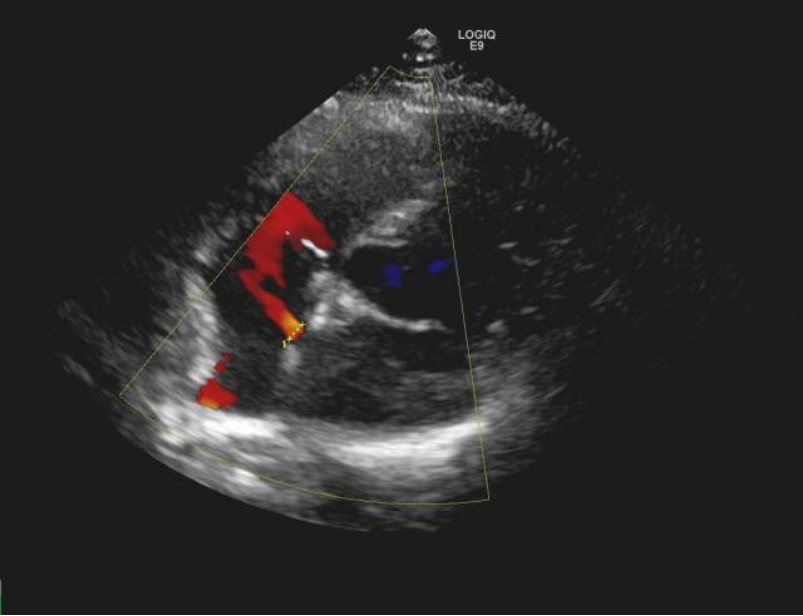

排除手术禁忌后,征得患者同意,手术由龙明教授、刘扬主任共同开展,在患者右侧股静脉穿刺点局麻后,送入导管行右心导管检查,准确测量肺动脉压、右房压、右室压、左房压,依据房缺大小选择封堵器,在DSA下封堵器被精准输送至房间隔缺损处一次性释放成功,术中超声医学科黄碧霞主任为患者行心脏彩超显示封堵器释放成型良好,无明显分流。牵拉实验提示封堵器固定牢固,且对二尖瓣、三尖瓣及上下腔静脉均无影响。整个手术过程严谨、配合有序,直至手术完成,用时还不到1小时。

该手术是根治常见房间隔缺损的有效办法。采用经股静脉穿刺的方法,将封堵器固定在房间隔缺损处,阻断心房分流,恢复正常血液循环途径。该手术避免了开胸,具有疗效确切、创伤小、出血量少、恢复快等优势,已成为先天性心脏病治疗的主流。